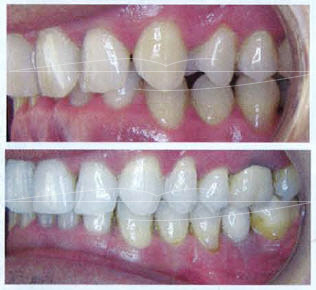

Comparaison des photos de sourire de face avant et après On remarque sur la photo du sourire de face l'encombrement disgracieux aux deux arcades associé avec une dysharmonie esthétique des axes et positions prémolo-molaires avec des dents relativements "jaunes", le sourire paraît vieux et vieillissant chez un adulte de 45 ans.

le traitement a permis en 15 mois et « trois rendez-vous orthodontiques» d'éclaircir le sourire alignant et réharmonisant les dents pour dégager un sourire plus blanc, mieux aligné et plus jeune, reflet d'une meilleur santé. le patient ressent une satisfaction fonctionnelle et esthétique qui lui permet de mieux partager et de recommander son expérience à son entourage.

Sans l'alignement et l'éclaircissement, la restauration implantaire serait passée inaperçue. l'absence d'appareillage fixe dans la bouche du patient a diminué la contrainte de la phase orthodontique et a facilité la pose de l'implant. II aurait été intéressant de coupler les séances orthos par des détartrages et soins parodontaux dans le même cabinet.